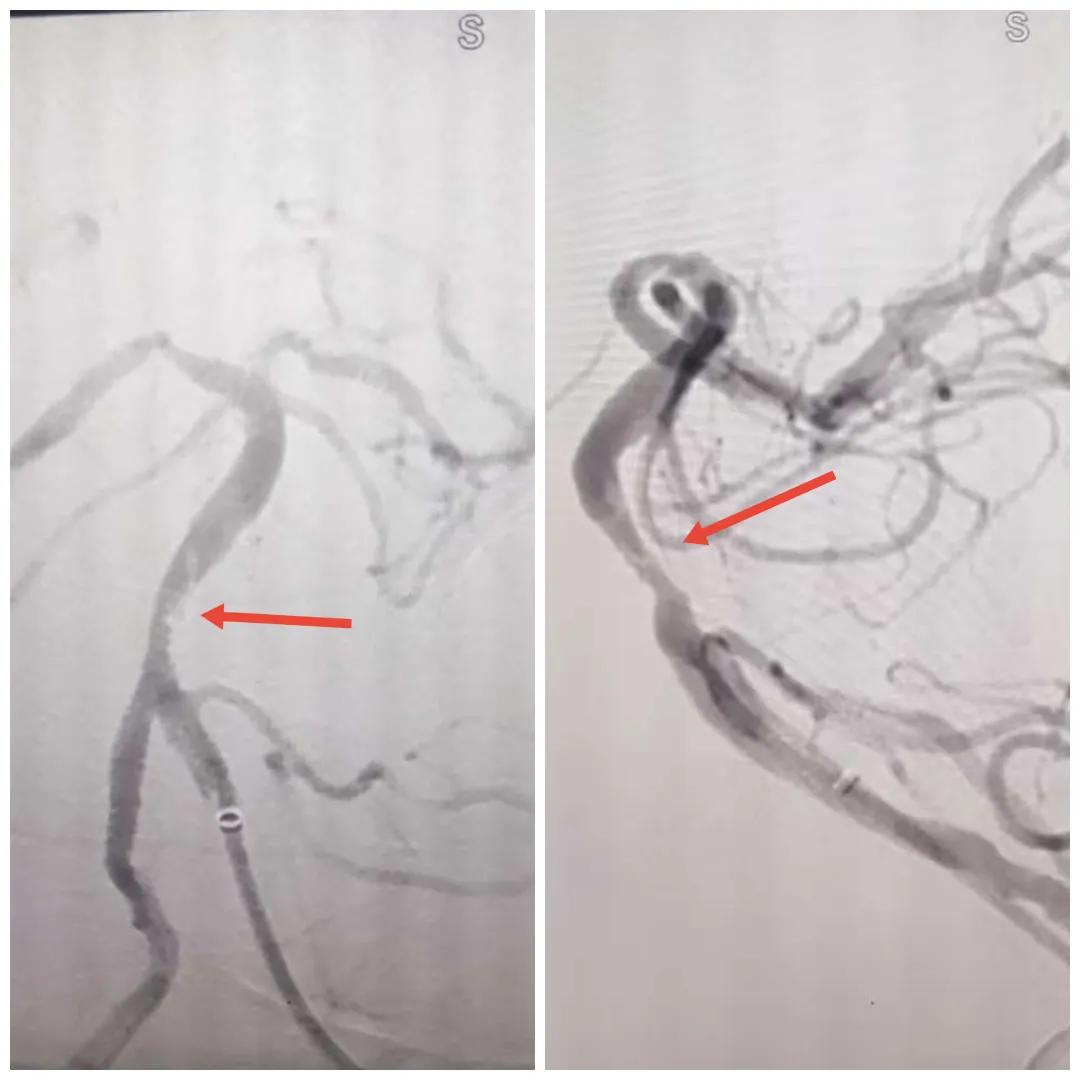

磁共振MRA提示基底動脈閉塞

在經(jīng)造影后,主刀醫(yī)生腦一科副主任楊慶堂發(fā)現(xiàn)患者基底動脈下段重度狹窄且狹窄段以遠有大負荷血栓,其狹窄處考慮為動脈夾層,手術(shù)難度及風(fēng)險較大。楊慶堂副主任在彭壯副主任醫(yī)師的協(xié)助下運用spaceman(太空人)技術(shù),中間導(dǎo)管抵近血栓抽吸配合支架拉栓,成功開通血管。再次造影可見基底動脈管腔明顯增寬,遠端血管顯影良好,且等待20分鐘后造影仍顯示血流通暢。楊慶堂副主任考慮到本次手術(shù)時間不宜過長,現(xiàn)患者基底動脈及分支前向血流維持良好,給予其抗栓藥物應(yīng)用后結(jié)束手術(shù),并建議患者3個月后復(fù)查造影,明確其基底動脈夾層情況。

造影可見血管夾層和大量血栓形成

取栓后血管管腔增寬,前向血流良好